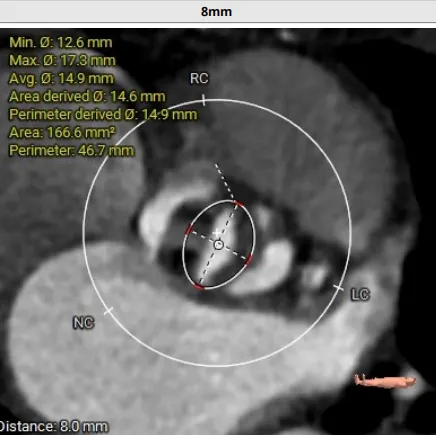

术前CT评估:TYPE 0型二叶瓣,瓣叶肥厚,前后交界粘连,瓣叶无明显钙化,双冠异窦,左冠开口高度约16.6mm,右冠开口高度约16.7mm。法式窦结构小,STJ高度约21.6mm,直径约24.4mm,升主动脉未见明显增宽,心脏角度约42°,左室大小尚可,心尖部可见局部心肌薄弱。

入路情况:主动脉弓部走行欠佳,主动脉弓部各主要分支开口处未见明显狭窄征象、未见发育变异,胸主动脉、腹主动脉走行较平直,管腔未见明显狹窄,双侧髂动脉-股动脉走形较平直,管腔未见明显狭窄,综合考虑,推荐右侧股动脉做为主入路,右侧股动脉穿刺水平管腔直径约为5.8mm,右侧股动脉分叉约在股骨头下1/3水平。

手术策略:多学科精心谋划,制定个性化策略